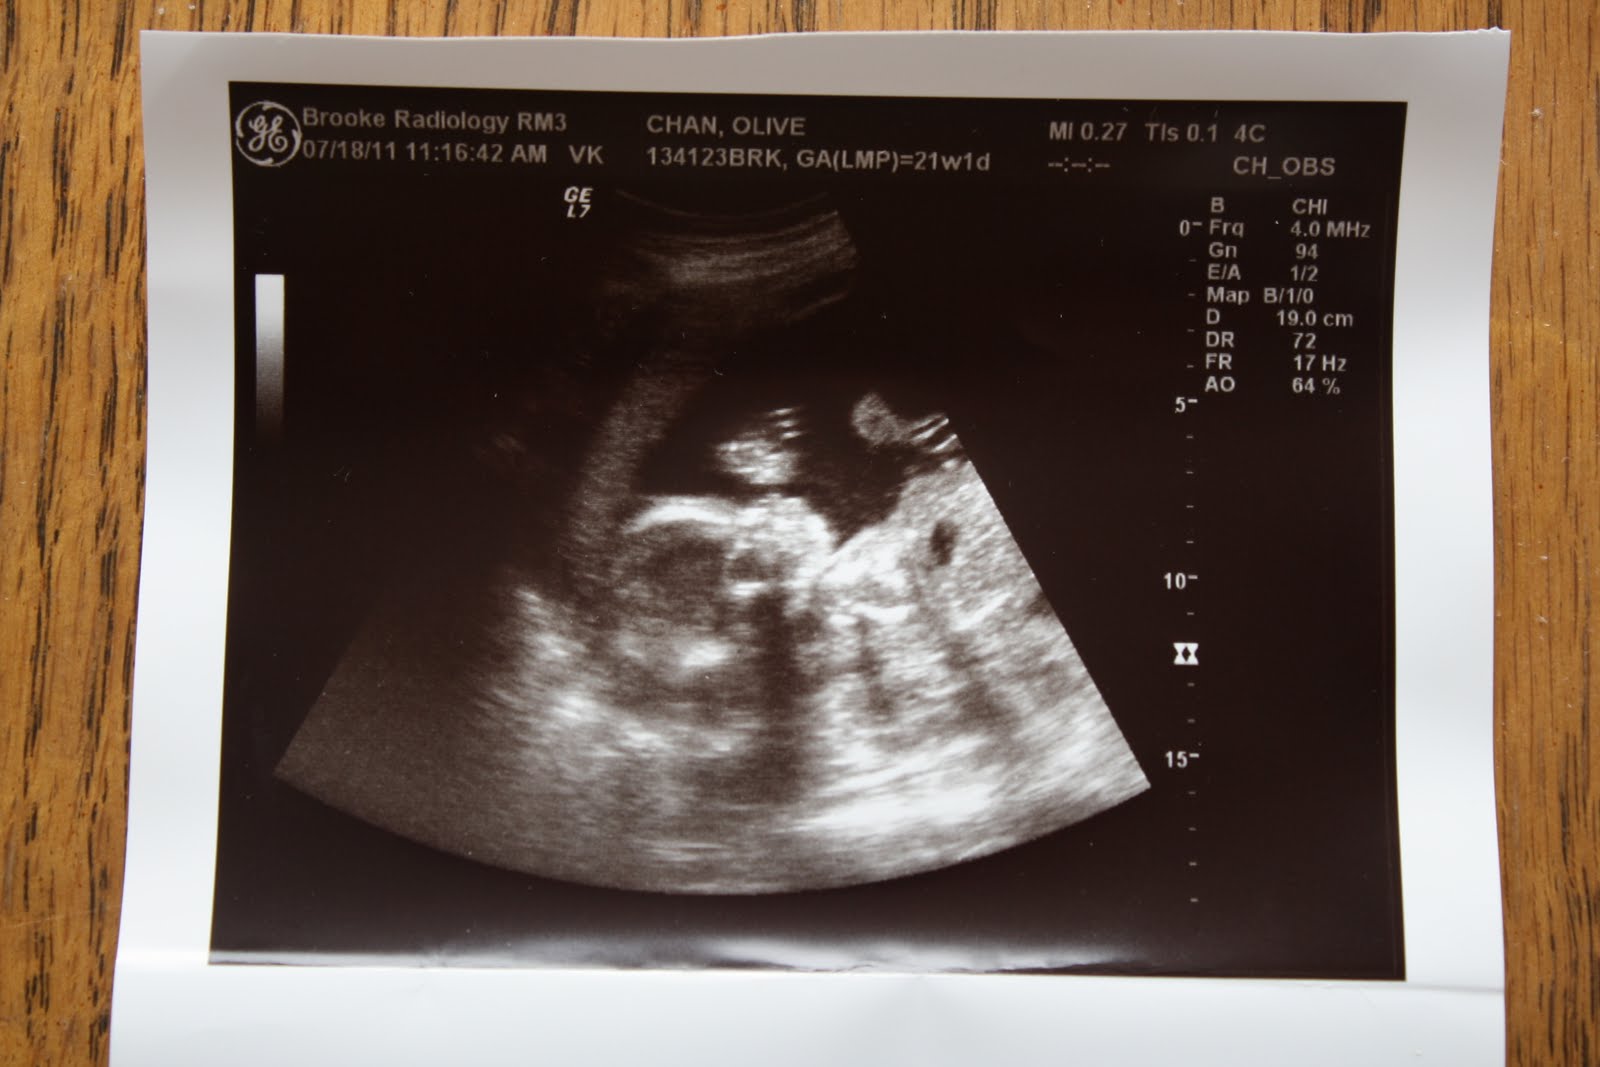

Here are a couple pics from the ultrasound.

Profile of the face.